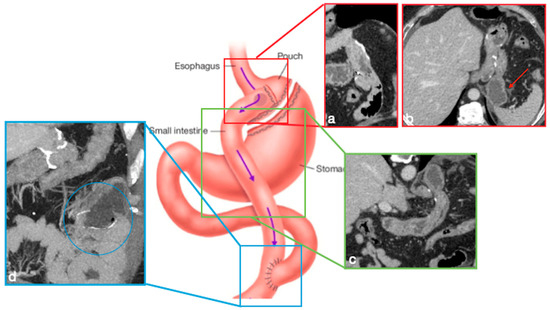

Figure 5. Gastric bypass. Surgical sutures seen at CT. Gastric pouch with gastrojejunostomy (a,b axial oblique view) and excluded stomach (b, arrow). Roux limb (c, coronal oblique view) of length of 75 to 150 cm from the jejunal division point for an average of 120 cm, jejunojenuostomy (d, circle, coronal view) between the biliopancreatic limb and the distal segment of jejunum (roux limb). The scheme was adapted from https://www.uptodate.com/contents/image/print?imageKey=GAST%2F79256 (accessed on 23 October 2022).

In RYGB, the transit of food along the gastrointestinal tract is rerouted to achieve a reduction in the absorptive capacity for calories. A small gastric pouch results from a surgical exclusion of the remnant stomach, followed by a gastrojejunostomy (between the new gastric pouch and the jejunum: alimentary limb) and a jejunojejunostomy (between the duodeno–jejunum channel and the jejunum–biliopancreatic limb), placed in communication in a common channel further downstream (Figure 5) [4,6].